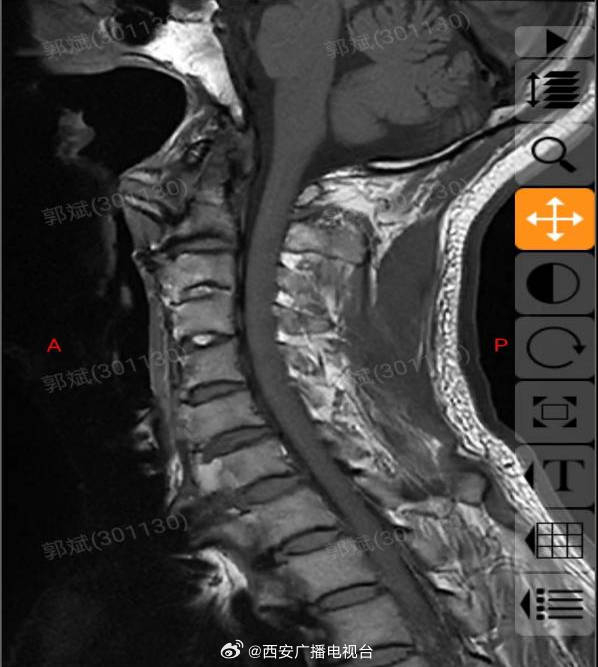

关于食管压迫型颈椎病的简单介绍

图片尺寸640x480

食管压迫型颈椎病,是由前纵韧带和骨膜撕裂导致,经治疗可缓解